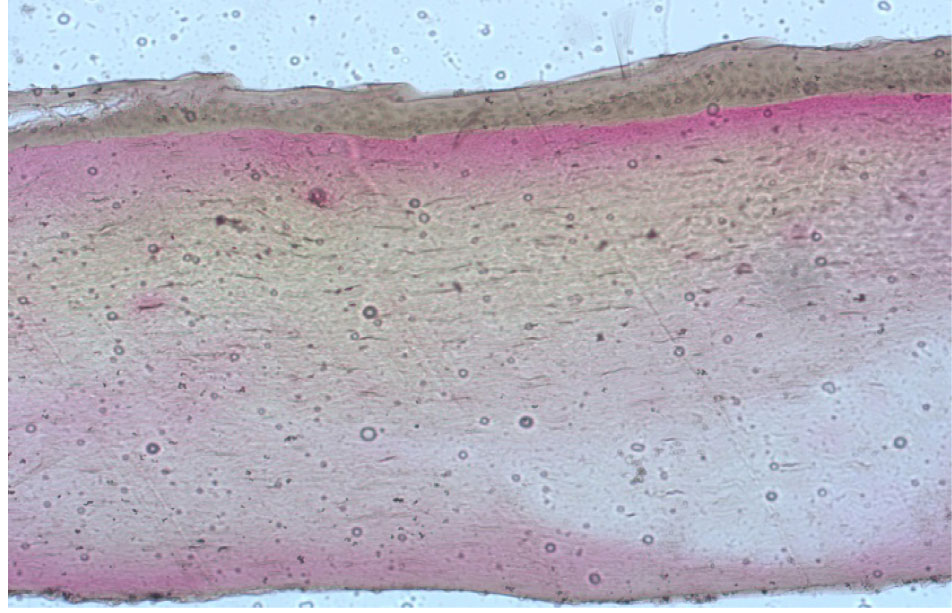

В группе интактных роговиц в препаратах визуализировались как сохранный эпителий с единичными мелкими зонами десквамации поверхностных слоев клеток, боуменова мембрана и стромальный слой с явлениями отека и набухания, но без наличия лакун между волокнами коллагена, что говорит о том, что интактный эпителий препятствует проникновению раствора рибофлавина в строму роговицы (рис. 7).